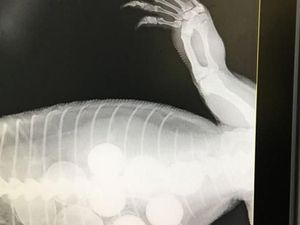

Goanna Telan Enam Bola Golf yang Dikira Telur

Seekor goanna berhasil pulih dari sakit perut parah setelah menelan enam buah bola golf dalam serangan di kandang ayam di utara New South Wales.